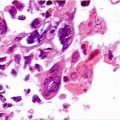

Direct examination of a sample taken from the vagina in saline solution: presence of guide cells, key cells, target cells or clue cells (epithelial vaginal cells with multiple superimposed bacteria in the cytoplasm). Where Mobiluncus is present, these pathogens may be identified via their characteristic shape and movement, as well as the formation of comma cells that have bacteria sticking to their surface in the same way as clue cells.

Bacterioscopy of vaginal swabs stained using the Gram technique show an absence of lactobacilli and polymorphonuclear cells with target cells and numerous cocobacilli or Gram-negative bacilli. The Nugent Score is considered to be the golden standard for the diagnosis of BV (Table 8.1).